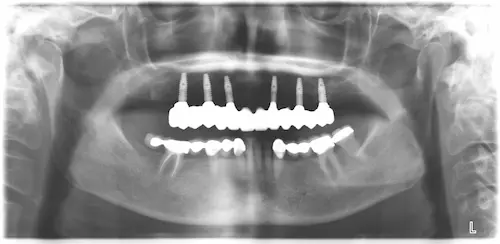

Ermittlung des Status Quo und schrittweise Planung

Bevor an einen operativen Eingriff gedacht werden kann, stehen als erstes Röntgenbilder mithilfe der Digitalen Volumentomographie auf dem Programm. Hier sind die Überreste in Ober-und Unterkiefer gut zu sehen, vor allem aber die Positionen der abgebrochenen Zahnwurzeln. Auf Basis der Bilder können die Positionen für die insgesamt 8 Implantate auf den Millimeter genau geplant werden: Unser Patient wird jeweils 4 Implantate im Ober-und Unterkiefer erhalten, die im Nachgang jeweils mit einem festsitzenden Zahnersatz versorgt werden. Die Einheilphase dauert zwischen 4 und 6 Monate, prognostiziert Dr. Mintert, der Spezialist für Implantate in der ZPK Herne.

Röntgenbild Kiefer - vor OP

Röntgenaufnahme - nach OP - All-on-Four